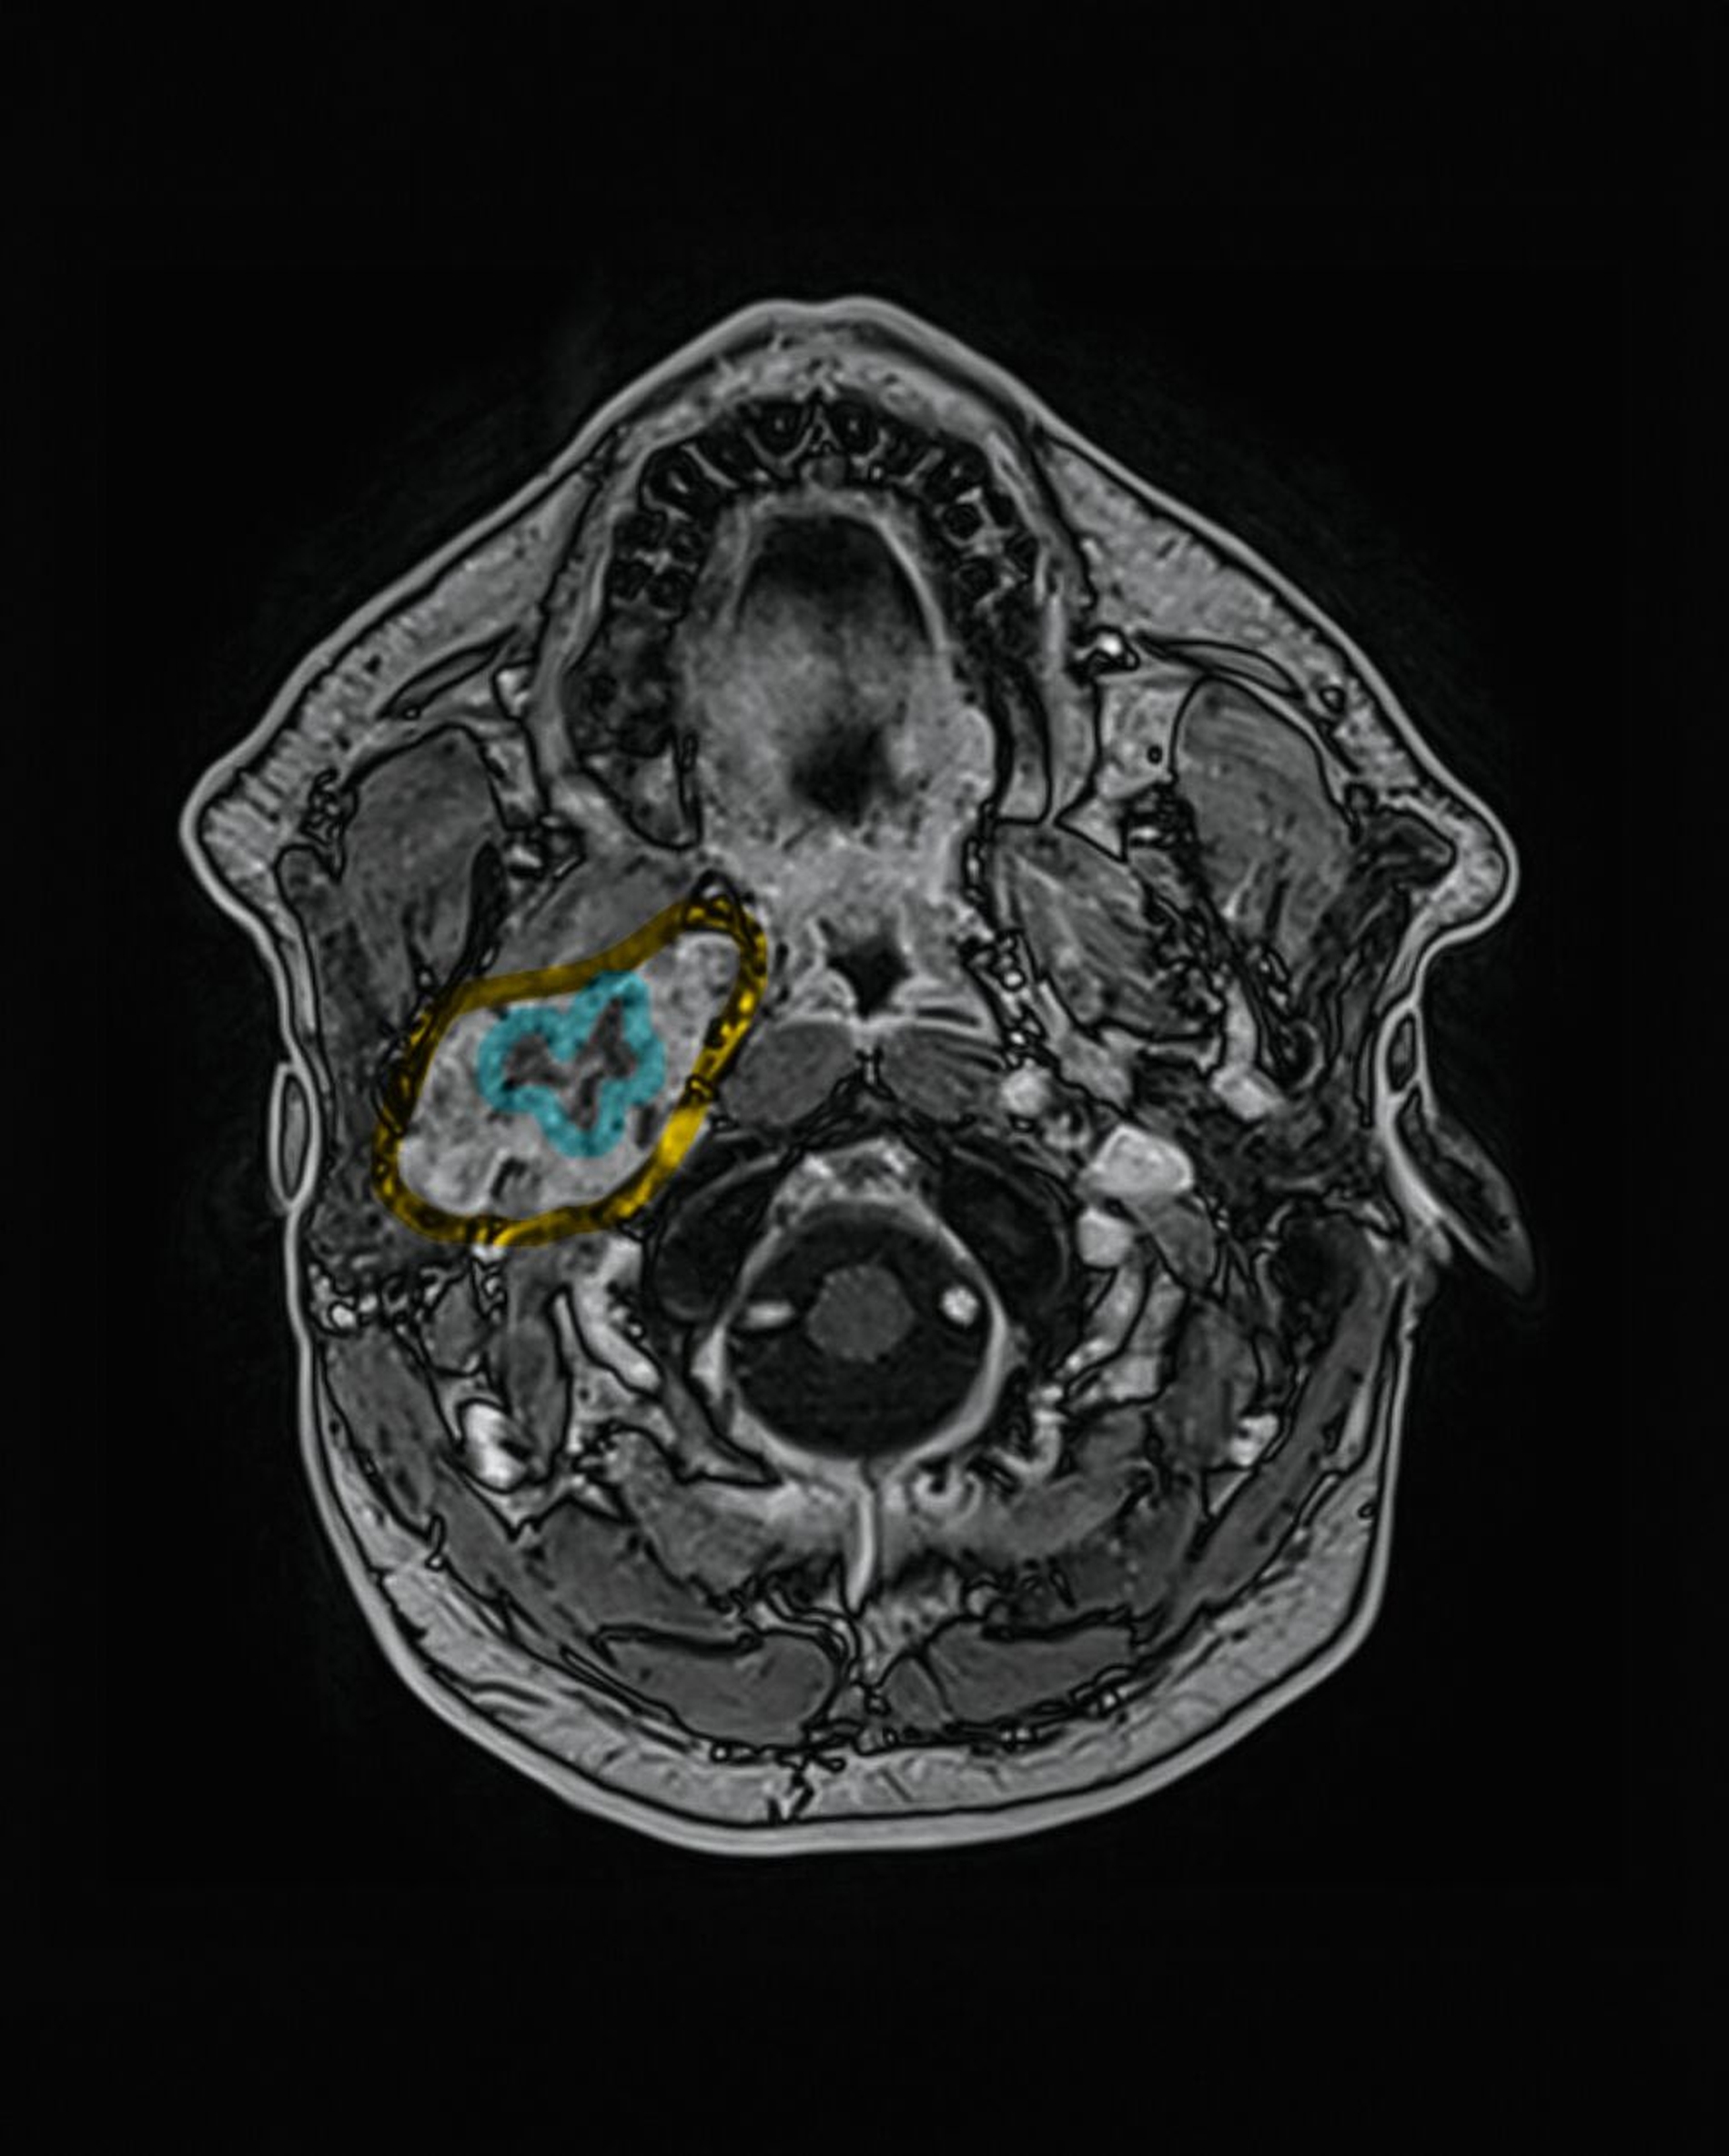

In der extern durchgeführten MRT der Halswirbelsäule vom 18. Dezember 2025 zeigte sich randständig eine angeschnittene Raumforderung im rechten Parapharyngeal- und Mastikatorraum, so dass eine gezielte weiterführende Bildgebung veranlasst wurde. Die kontrastmittelgestützte MRT vom 30. Dezember 2025 ergab eine inhomogene, gut abgrenzbare Raumforderung im rechten Parapharyngeal- und Mastikatorraum mit einer maximalen axialen Ausdehnung von 52 mm x 28 mm.

Die Läsion offenbarte ein zum Muskel isointenses T1-Signal sowie gemischt hyper- und hypointense Anteile in T2-gewichteten Sequenzen. Nach Kontrastmittelgabe imponierte eine kräftige, inhomogene Anreicherung; zentral bestanden nekrotische Areale. Eine Diffusionsrestriktion war inhomogen ausgeprägt.

Ein vaskulärer Ursprung konnte mittels dynamischer Sequenzen ausgeschlossen werden. Die Raumforderung wuchs verdrängend bis an den Musculus pterygoideus heran und hatte einen langstreckigen Kontakt von > 90° zur A. carotis interna. Zusätzlich bestand eine schlitzförmige Kompression der V. jugularis interna sowie eine fokale Teilthrombosierung der V. facialis communis. Pathologisch vergrößerte Lymphknoten waren nicht nachweisbar.